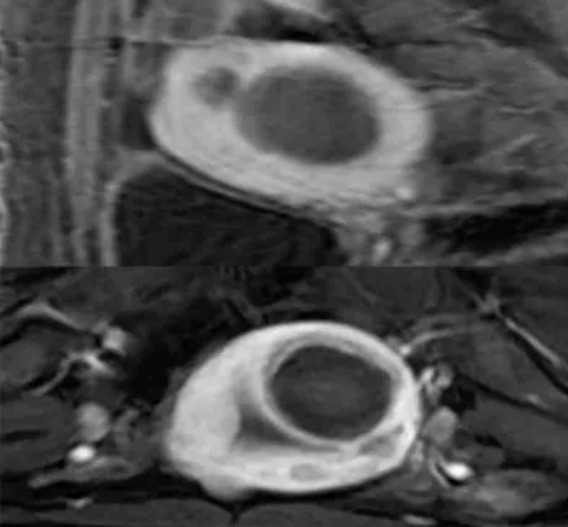

术前MRI平扫及增强扫描可鉴别子宫肌瘤与隐匿性子宫平滑肌肉瘤。弥散加权成像(DWI)高信号、表观弥散系数(ADC)低信号及强化不均是子宫肉瘤的典型影像学表现;MRI的T2加权成像(T2WI)信号可评估消融难度,若T2WI高信号则提示肌瘤含水量高,消融难度通常大于T2WI低信号的病灶。

图:MRI显示一个约9厘米的肿瘤

图:DWI显示高信号强度、

图:MRI显示肿瘤的ADC值较低